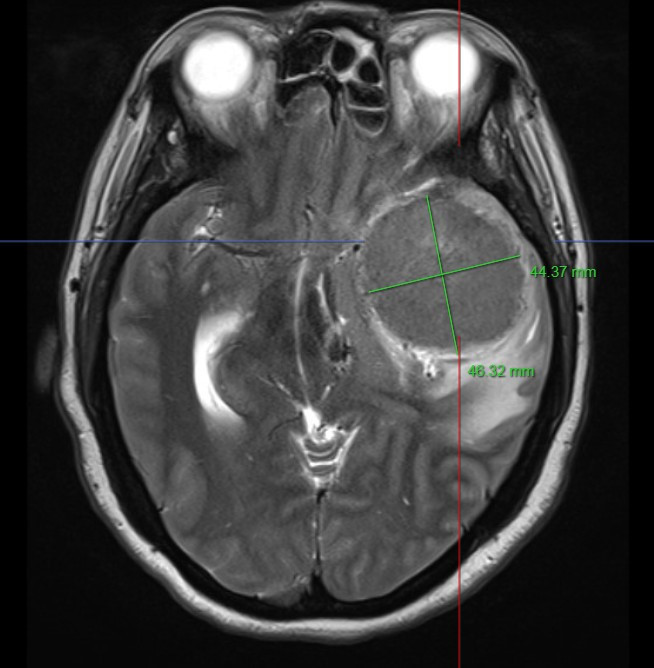

Sau khi được thực hiện các xét nghiệm lâm sàng cần thiết, chụp cộng hưởng từ kết quả cho thấy người bệnh có một khối u màng não vùng hố thái dương trái với kích thước rất lớn khoảng 50mm x 70mm.

Hình ảnh: Chụp cộng hưởng từ sọ não của người bệnh phát hiện khối u khổng lồ |

Hình ảnh: Chụp cộng hưởng từ sọ não của người bệnh phát hiện khối u khổng lồ